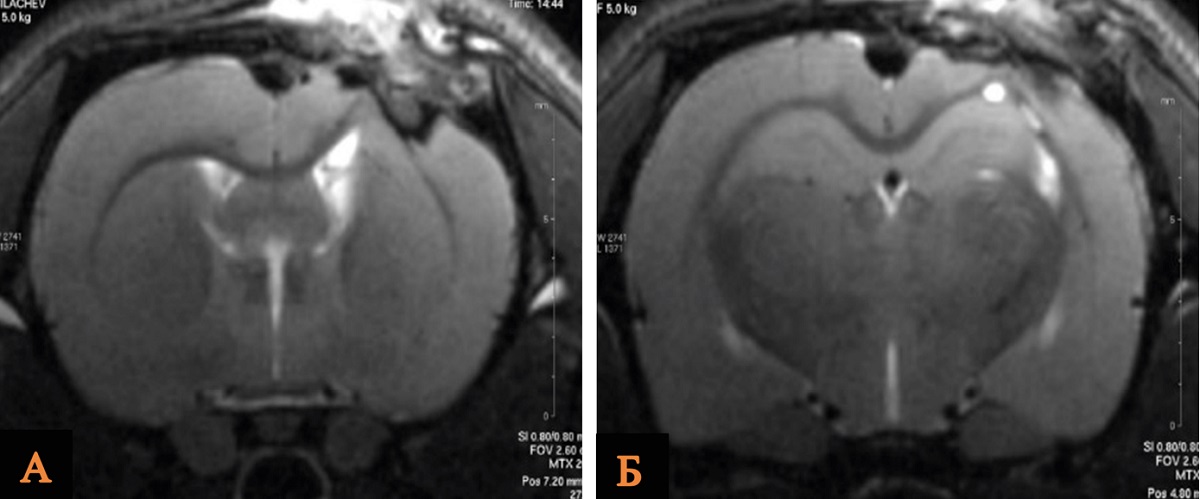

При изучении объема повреждения головного мозга крыс после ОЧМТ при введении хлорида лития в дозе 63 мг/кг через 180 мин проведено исследование объема повреждения головного мозга крыс по данным морфометрического анализа МР-изображений в группах ложнооперированных животных (n = 10), группе Контроль (n = 10) и ОЧМТ+Литий 180 мин/63 мг (n = 10).

Анализируя полученные данные, мы выявили, что средний объем повреждения головного мозга крыс был статистически значимо меньше в группе ОЧМТ+Литий 180 мин/63 мг, чем в группе Контроль. По данным МРТ, исследуемый показатель в группах сравнения составил 28,0 и 35,0 mm3 соответственно (рис. 3, табл. 3).

Рис. 3. МРТ зоны ушиба головного мозга крысы после введения хлорида лития в дозе 63 мг/кг через 180 мин в сравнении с контрольной группой

Примечание: А – группа Контроль; Б – группа ОЧМТ+Литий 180 мин/63 мг. Изображение авторов, получено в ходе оригинального исследования.

Таблица 3

Объем повреждения головного мозга крыс в группе ОЧМТ+Литий 180 мин/63 мг и группах сравнения по данным МРТ-изображений на 14-е сутки наблюдения

Группа | Объем повреждения головного мозга мм 3 | p, значимость относительно ложнооперированных животных | p, значимость относительно контрольных животных |

Ложнооперированные животные (n = 10) | 12,0 [8,0–14,5] | – | – |

Контроль (n = 10) | 35 [30–36] | 0,0001 | – |

ОЧМТ+Литий 180 мин/63 мг (n = 10) | 28 [23–30,5] | 0,001 | 0,03 |

Примечание: составлено авторами.